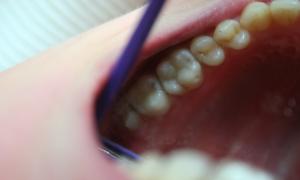

Chrup s amalgámovými výplňami

Výmena amalgámových výplní fotokompozitnými plombami s estetickým a anatomickým tvarom zubu